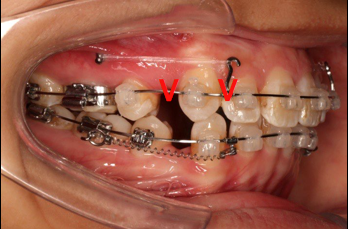

4.第6个月:2017.04.28 ◆ 上0.016*25ss 13/23v形曲,下0.017*25ss

2017.04.28  上0.016*25ss 13、23近远中约5度 v形曲,下0.017*25ss

上颌使用高位种植钉及长牵引钩,配合尖牙近远中的v-bend,上颌前牙的牙齿移动方式是整体往上,往后内收。

下前牙的压低+控制性倾斜移动内收,改善唇倾度,磨牙通过powerarm 直立,控根整体近中移动,使咬合高点的前移,整平下颌同时进行内收。

上后牙:高度保持不变/压入性移动,尽量避免伸长;▲垂直向控制中,应防止上后牙颊侧倾斜(TPA);▲腭尖高度控制也重要。

下后牙: 向前,整体移动利于咬合支点前移(Power arm);▲向前,倾斜移动易导致咬合平面后下旋转;▲后牙压低/全牙弓压低利于咬合平面逆时针旋转。

上前牙:向后,向上整体移动;

下前牙:向下,向后控制性倾斜移动。